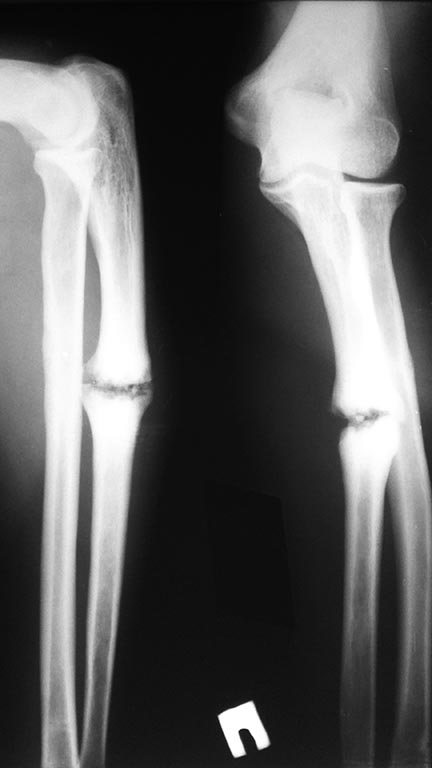

Ложный сустав локтевой кости

Здравствуйте, уважаемые коллеги! Пациент 30 лет, социально адаптированный, травма год назад, не лечился.

На данный момент беспокоит только деформация предплечья (языком пациента шишка на руке), планирую выполнить резекцию ложного сустава, остеосинтез пластиной с костной пластикой.Интересно послушать мнение коллег.